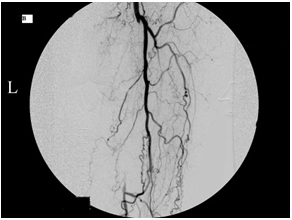

This 75-year-old man’s primary care doctor referred him to my clinic because of left leg cramps after ambulating a few blocks and I found that his left superficial femoral artery was occluded (left column images). Using catheters, wires, balloons, and a covered stent, I restored blood flow through the blocked artery and his problem resolved (right column images).